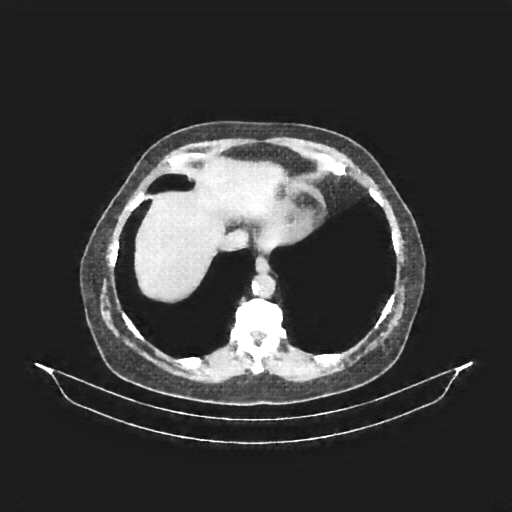

Original NATIVE CT scan (input)

Full window (WL 1023.5, WW 4095 β†’ Low βˆ’1024, High +3071)

Actual HU range: [-160.0, 240.0]